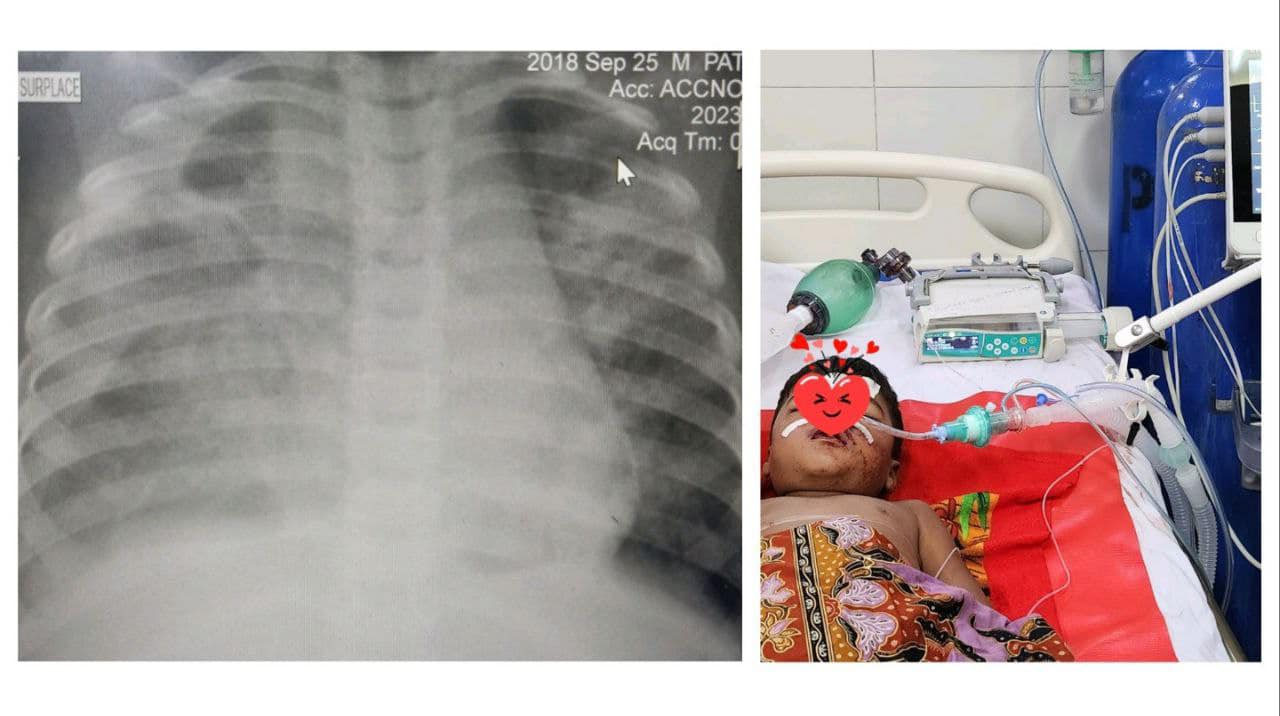

កុមារាតូចអាយុ៤ឆ្នាំរូបនេះ បញ្ជូនមកពីមណ្ឌលសុខភាពមួយនៅខេត្តត្បូងឃ្មុំ ក្រោយដាក់សេរ៉ូមអស់៣លីត្រ។ កុមារានេះមានជំងឺគ្រុនឈាមកម្រិត៤ចុងក្រោយយ៉ាងធ្ងន់ធ្ងរបំផុត (EDS) អស់ជីពចរ សន្លប់ ហូរឈាម ខ្សោយដង្ហើម ខ្សោយថ្លើមនិងតម្រងនោម #អស់ជីពចរ៦ដង (6 times repeated cardiovascular collapses-shocks)។

ក្នុងរយៈពេល៤៨ម៉ោងនៅក្នុងបន្ទប់សង្គ្រោះបន្ទាន់នៃមន្ទីរពេទ្យគន្ធបុប្ផា ត្រូវបានសង្រ្គោះជីវិត ដោយប្រើឈាមនិងប្លាស្មាអស់៦ប្លោក និងបញ្ចូលប្លាកែតអស់៤ប្លោក ជាមួយការសង្រ្គោះដោយម៉ាស៊ីនសប់ដង្ហើម៣ថ្ងៃ ថ្ងៃនេះ កូនតូច ត្រូវបានជួយសង្គ្រោះជីវិតនៅមន្ទីរពេទ្យគន្ធបុប្ផាភ្នំពេញ។